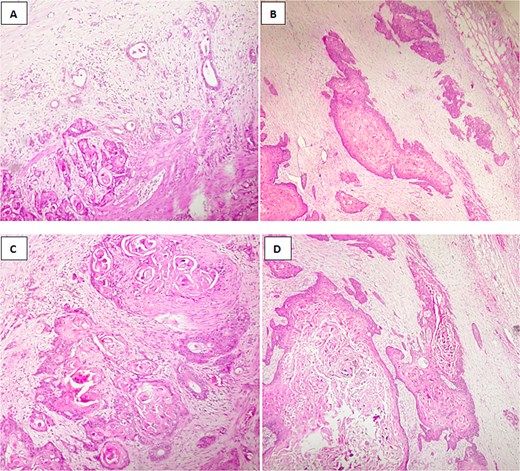

Microscopic findings revealed a squamous component arranged in nests, clusters with keratin pearls;consists of atypical polygonal cells with intercellular bridges, showing, high nuclear to cytoplasmic ratio, irregular nuclear rim, prominent nucleoli, and abondant eosinophilic cytoplasm,a glandular component consisted of mucinous cells,with lymphovascular and perineural invasion, and tumor extension into adjacent liver (Fig. 4A–D).

Histological image of adenosquamous carcinoma of the gallbladder showing both glandular and squamous components, with evident areas of keratinization. (A, B) H&E stain, ×100; (C, D) H&E stain, ×200.